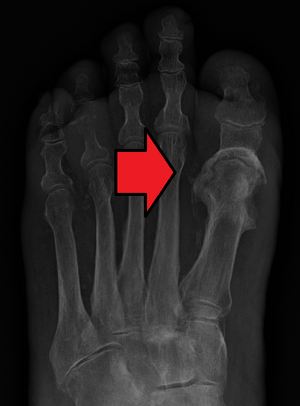

| Osteomyelitis of the 1st toe | |

Osteomyelitis (OM) is the infectious inflammation of bone marrow.[1] Symptoms may include pain in a specific bone with overlying redness, fever, and weakness.[1] The feet, spine, and hips are the most commonly involved bones in adults.[2]

Radiographs and CT are the initial method of diagnosis, but are not sensitive and only moderately specific for the diagnosis. They can show the cortical destruction of advanced osteomyelitis, but can miss nascent or indolent diagnoses.[23]

Diagnosis of osteomyelitis is often based on radiologic results showing a lytic center with a ring of sclerosis.[13] Culture of material taken from a bone biopsy is needed to identify the specific pathogen;[27] alternative sampling methods such as needle puncture or surface swabs are easier to perform, but cannot be trusted to produce reliable results.[28][29]